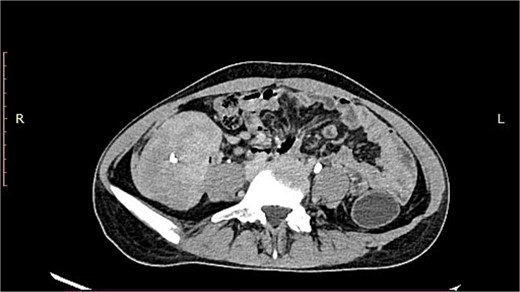

A 19-year-old woman presented with a 15-day history of severe abdominal pain and a palpable mass, with no history of hematemesis or perforation. Contrast-enhanced computed tomography revealed a well-defined solid lesion with calcification arising from the terminal ileal wall, prompting suspicion of a GIST (Fig. 1). Surgical excision of the terminal ileum, caecum, and appendix was performed for further assessment.

CT image showing a well-defined smooth lobulated heterogeneously enhancing mass lesion in the right paracolic gutter and right iliac fossa, with calcific focus within.